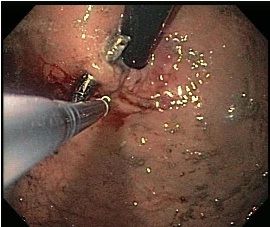

In the digestive tract, the magnets can aggregate and cause sequelae as grave as intestinal torsion and blood poisoning. The images at left show a radiograph demonstrating multiple magnets connected in the stomach (left), which on an endoscopic retroflex view of the stomach cardia and gastroesophageal junction (below) were pinching mucosa and causing pressure ulceration. Forceps are visible trying to dislodge the magnets.